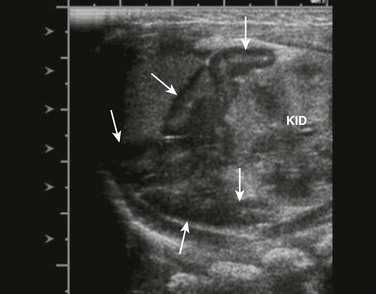

На УЗИ тимус гипоэхогенный в сравнении с щитовидной железой, и изоэхогенный миакарду. Контур тимуса четкий; ровный по передней поверхности, но волнистый сзади. У детей младшего возраста эхо-структура железы однородная мелкозернистая, а у старших детей и взрослых точечные гипо- и гиперэхогенные сигналы перемежают — это смесь жира и лимфоидной ткани. Внутри тимуса можно разглядеть тонкие гиперэхогенные фиброзные перегородки, которые делят железу на отсеки. Из-за фиброзной капсулы края тимуса хорошо контурируют. Расположение, форма и размер тимуса сильно варьируют.

| Фото. А — Шейная (стрелки) и грудная (треугольники) части нормального тимуса. Б — Шейная часть нормального тимуса на поперечном срезе. В — Шейная часть нормального тимуса (черные стрелки) у мальчика 12-ти лет на продольном срезе крепится к нижнему полюсу щитовидной железы (белая стрелка) щитовидно-тимусовой связкой (треугольник). Обратите внимание на картину «звездного неба» — это гиперэхогенный жир на фоне гипоэхогенной лимфоидной ткани. | ||

| Фото. А — Поперечный срез тимуса у новорожденного. Б — У детей раннего возраста, особенно при крике, верхняя часть тимуса может подниматься на шею через яремную вырезку, тогда он определяется позади щитовидной железы (звездочка). В — На саггитальном срезе хорошо видно, что тимус (эктопическая долька на шее) гипоэхогенный по сравнению с щитовидной железой. | ||